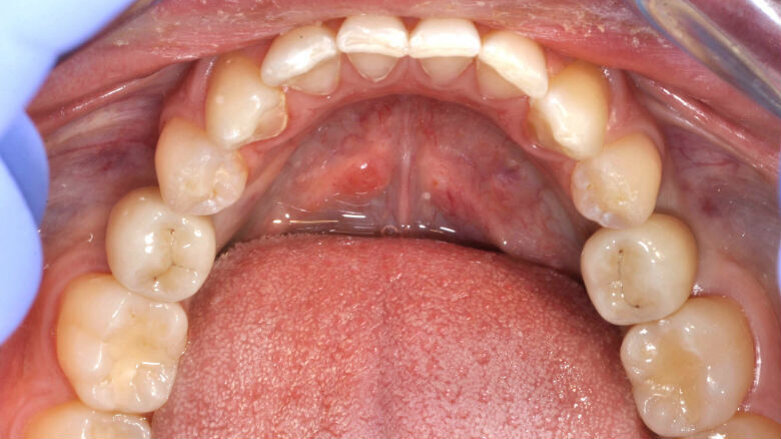

Fig. 17_Dettaglio tragitto transmucoso.